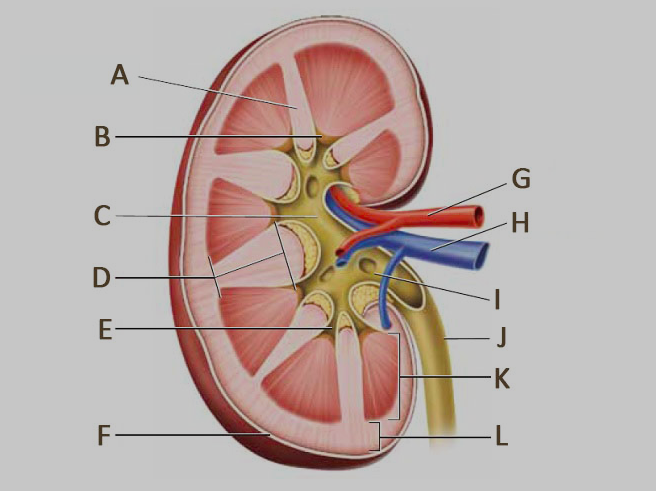

Calyx (of the kidney)

Medullary pyramids

Renal artery/vein

Renal capsule

Renal columns

Renal cortex

Renal medulla

Renal Pelvis

Ureter